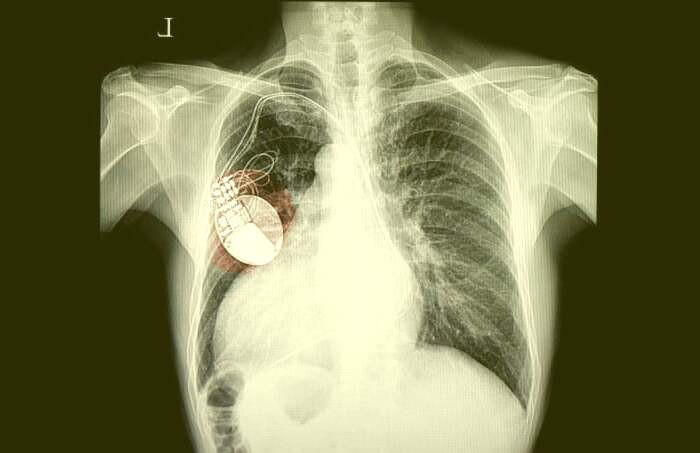

باتری قلب یا پیس میکر، که به آن ضربان ساز نیز گفته میشود، یک دستگاه پزشکی با بار الکتریکی است که کند بودن ضربان قلب فرد را تشخیص داده و با ارسال یک جریان الکتریکی، ضربان منظم و طبیعی را ایجاد میکند. این دستگاه پزشکی مهم، به طور دقیق و مداوم ضربان قلب را کنترل کرده و در صورت نیاز، با ارسال جریان الکتریکی مناسب، ضربان قلب را به حالت طبیعی بازمیگرداند. این فرآیند به طور مداوم و خودکار انجام میشود تا سلامت و ریتم طبیعی ضربان قلب فرد حفظ شود. در ادامه این بخش از بهداشت و سلامت نمناک، با جزئیات بیشتری در مورد نحوه کارکرد باتری قلب آشنا خواهید شد.

باتری قلب مصنوعی مدرن، دو بخش دارند.یک قسمت، که مولد پالس نامیده می شود، شامل باتری و لوازم الکترونیکی است که ضربان قلب شما را کنترل می کند. بخش دیگر یک یا چند هدایت کننده است که منجر به ارسال سیگنال های الکتریکی به قلب می شود. هدایت کننده ها سیم های کوچکی هستند که مولد ضربان به قلب شما هستند. جراح شما برای کمک به مدیریت ضربان قلب نامنظمتان به نام آریتمی، آن را زیر پوست قرار می دهد.

کاشت معمولاً یک تا دو ساعت طول می کشد. نصب باطری قلب نیازمند انجام یک جراحی جزئی در یک بیمارستان یا یک آزمایشگاه مخصوص درمان بیماری های قلبی است. پیش از جراحی، به فرد داروی آرام بخش تزریق می شود و پزشک محل نصب باطری را برای جلوگیری از احساس درد، بی حس می کند. پزشک برای جلوگیری از عفونت ممکن است به شما آنتی بیوتیک بدهد.

سپس به یک سیاهرگ بزرگِ نزدیک شانه سمت مخالف دست غالبتان سوزنی را وارد کرده و سپس با استفاده از هدایت فلوروسکوپی (دیدن تصاویر اشعه ایکس به صورت زنده) با این سوزن از طریق سیاهرگ سیم های باطری را به جای مناسبی در قلب می فرستد.

بعد از قرار گرفتن سیم ها در محل مناسب پزشک با ایجاد یک برش کوچک در پوست سینه یا شکمتان محفظه فلزی کوچک باطری را به زیر پوست فرستاده و سر آزاد سیم های منتهی به قلب را به آن وصل می کند. باطری و ژنراتور آن در این محفظه قرار دارند.